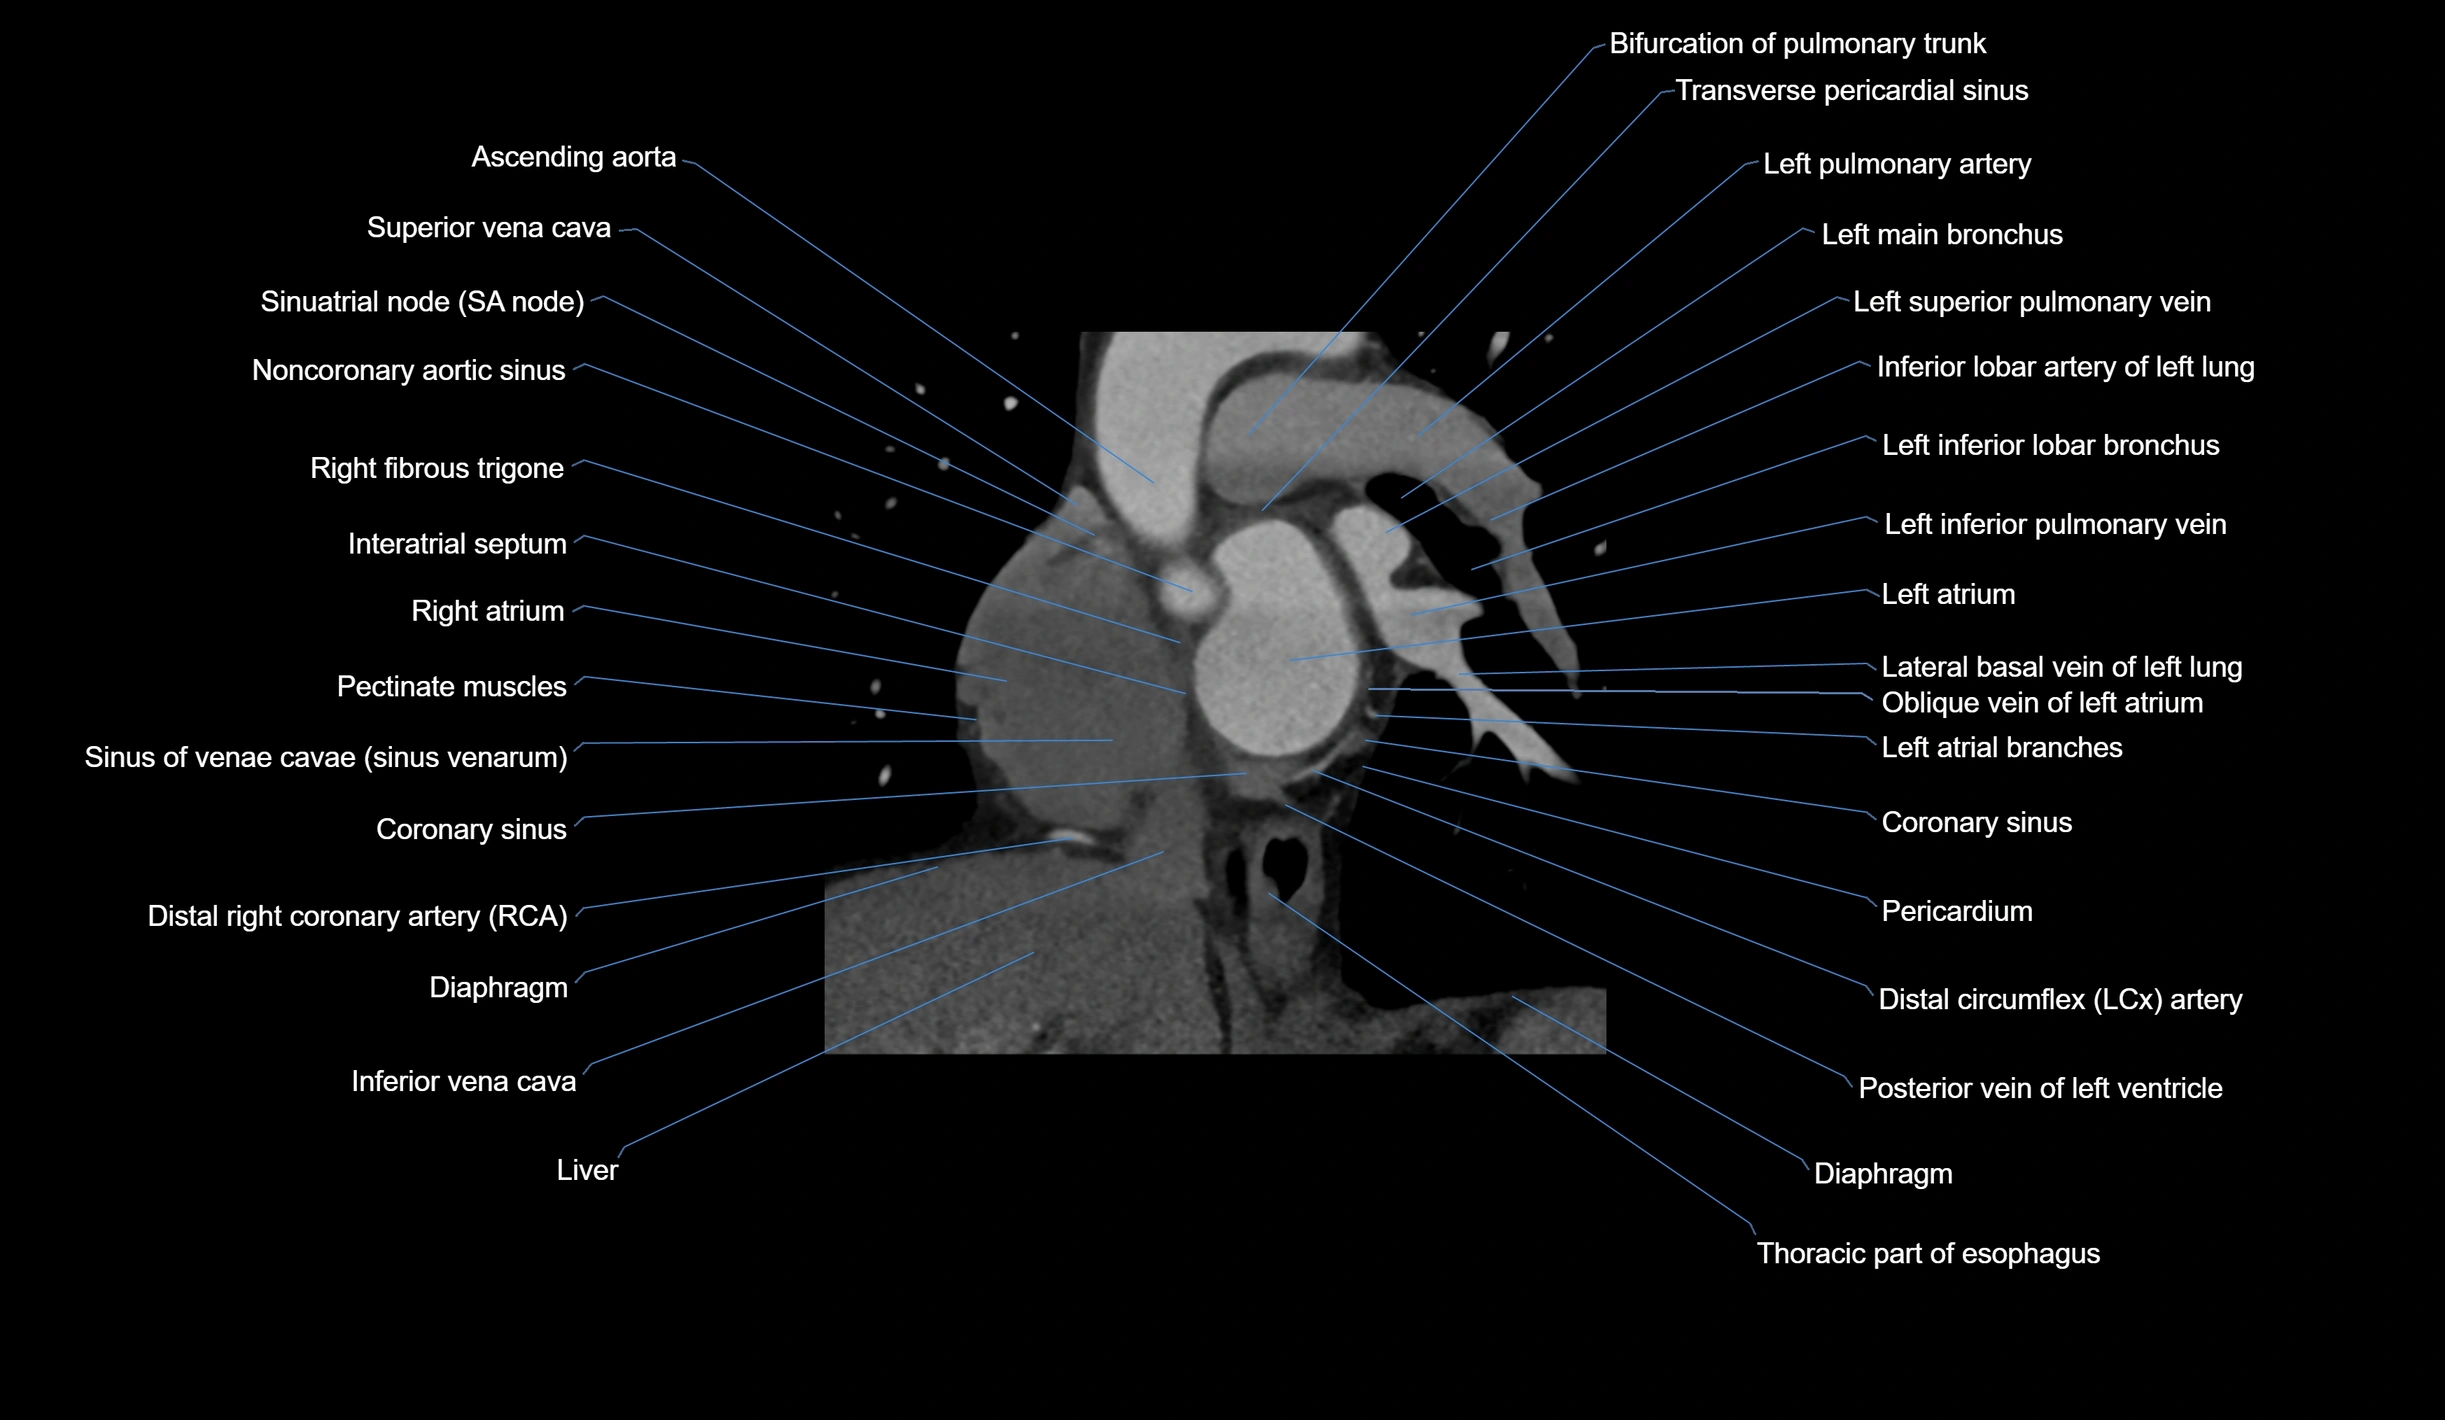

CT Appearance

Non-contrast CT (Calcium Scoring):

-

AM artery visualized for coronary calcium scoring

Calcified plaques appear as hyperdense foci; scored with Agatston method

CT Coronary Angiography (CCTA):

Best non-invasive modality for acute marginal artery visualization

Shows origin, course along the acute margin, and right ventricular branches

Detects stenosis, occlusion, calcified and non-calcified plaques, aneurysm, or anomalous course

Multiplanar reformats and 3D reconstructions help in pre-PCI and surgical planning

Critical for assessing right ventricular infarction risk in RCA disease

MRI image

CT images